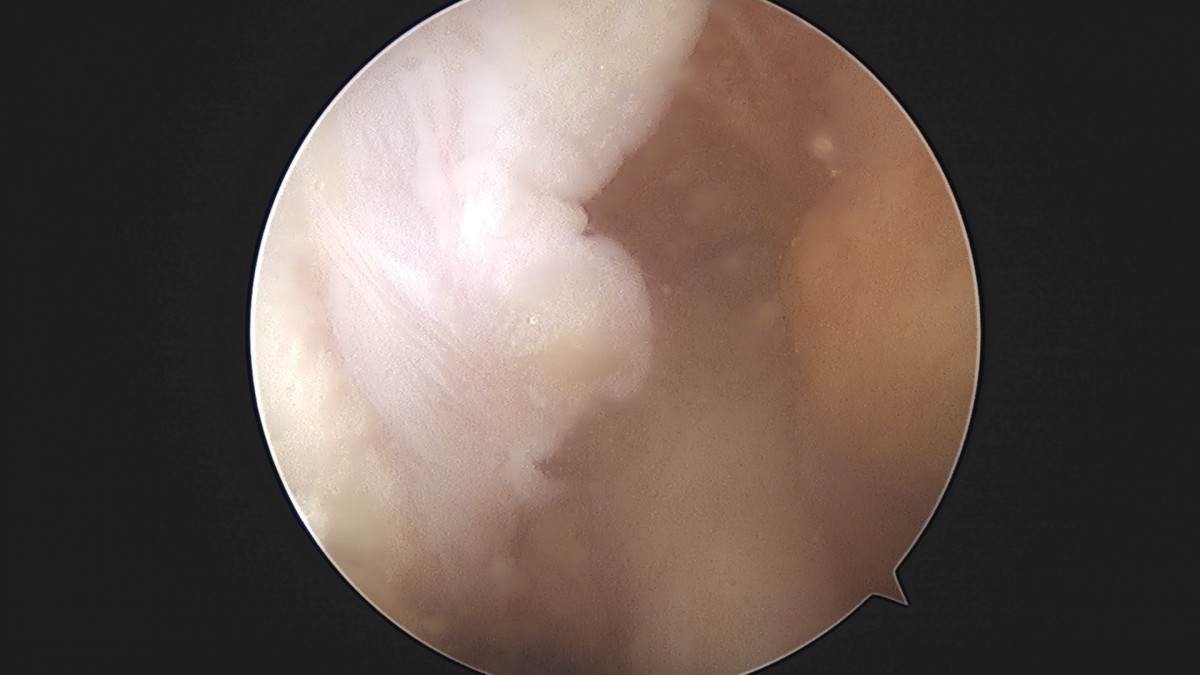

이재상원장님 무릎 활막절제술 및 추벽절제술 신욱O 환자

작성자 최고관리자 댓글 0건 조회 872회 작성일 25-01-13 15:13